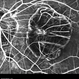

- macular hole, posterior staphyloma, degenerative myopia, high myopia, myopic eye, vitreoretinal degeneration

- Macular hole retinal detachment over a posterior staphyloma of pathologic myopia.